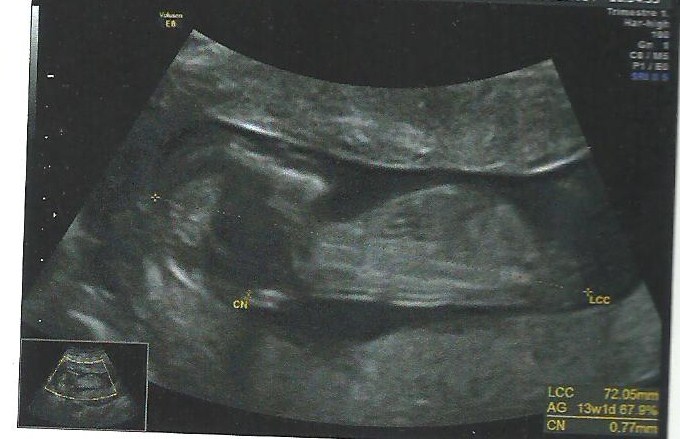

anyone care to take a guess at my scan ?

only picture we could get , baby would not stay still !!

i don't know if you can see anything , nub ? skull ?

all guesses are welcome x

A&J I hope I'm wrong but this looks girl to me.

I'd say boy x

Way to dark for me to guess.

Sorry, I'm not seeing clues, it's rather dark to see if anything is even there.

Can't see a nub but getting a girly vibe xx